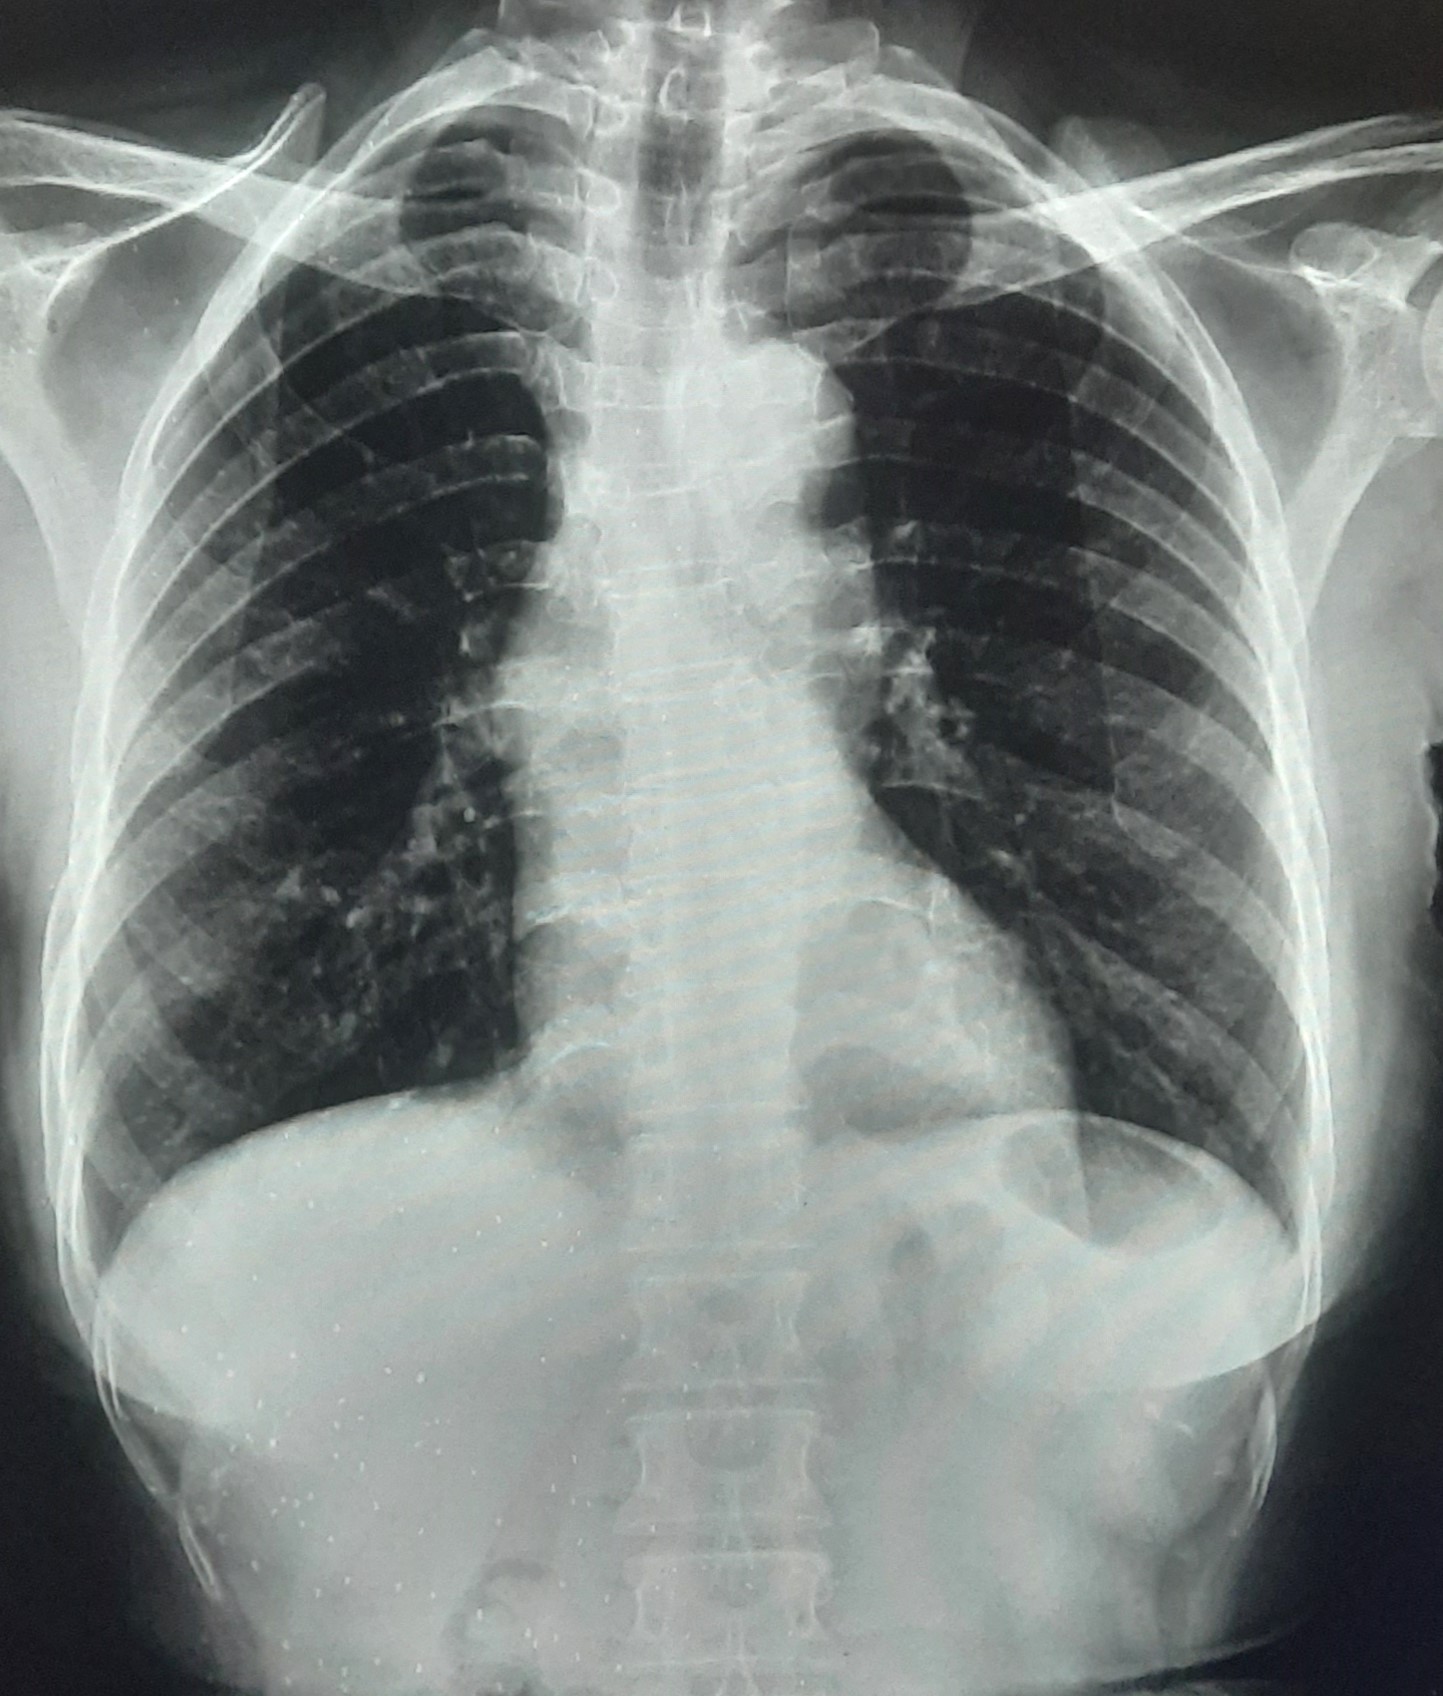

| 251 | IGGMC, Nagpur, Nagpur | P2 | 29-4221 | Ganpat Gaikawad | Consent taken on Paper | 70 Yrs. |

Provisional Diag : post TB sequele?

Final Diag : Fibrosis |

Non-TB Case (Confirmed) | Fibrosis | Abnormality visible on x-ray |